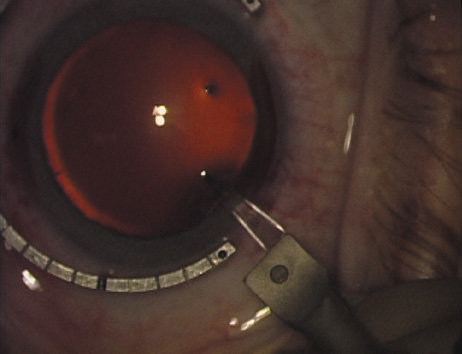

Fig. 10. The single footplate diamond blade is inserted perpendicular to the corneal surface and at the peripheral most extent of clear corneal tissue. In this case, the nomogram calls for arcuate incisions of 45 degrees. Therefore, the incision is begun approximately 22.5 degrees to one side of the broad hash mark. (Reprinted from Hardten DR, Lindstrom RL, Davis EA. Phakic Intraocular Lenses: Principles and Practice. Thorofare, NJ: SLACK Incorporated, 2004, with permission.)

Fig. 11. Opposite relaxing incision is completed. (Reprinted from Hardten DR, Lindstrom RL, Davis EA. Phakic Intraocular Lenses: Principles and Practice. Thorofare, NJ: SLACK Incorporated, 2004, with permission.)